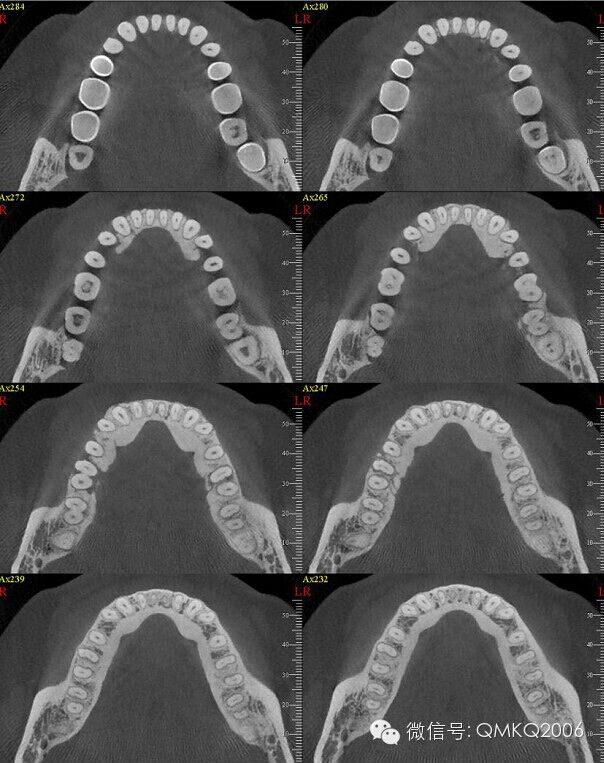

誤區(qū)13 嚴(yán)重的牙周炎不能矯正

很多正畸醫(yī)師對(duì)此望而生畏。嚴(yán)重的牙周炎常有明顯的病理性牙移位或松動(dòng),但牙齒矯正同時(shí)也是在治療牙周病,施以生物限度內(nèi)的矯治力非但不會(huì)使牙周病惡化,反而會(huì)改善病情。未經(jīng)治療或控制的牙周炎不能矯正,但穩(wěn)定的牙周炎可以,這是不同專業(yè)的醫(yī)師共同合作才能完成的治療,對(duì)醫(yī)師是個(gè)考驗(yàn)。